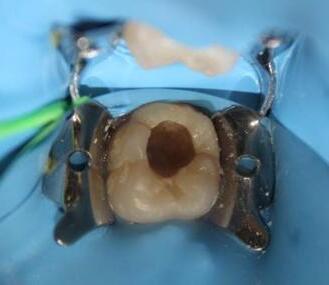

8.Biodentine®AnalternativeinVitalPulpTherapyinYoungPermanentTeeth.ClinicalCase,40monthFollow-Up. (Pgs.88-96)

Biodentine®UnaalternativaenlaTerapiaPulparVitalenDientesPermanentesJóvenes.CasoClínico.Seguimientode40Meses.

LuisDavidRamosFlores,DDS,